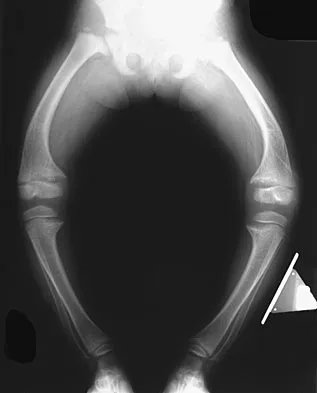

Figures 32a and 32b show the AP and lateral radiographs of an 11-year-old boy who has a severe limp, a fever, and swelling and tenderness of the thigh. Aspiration of the bone reveals purulent material. The patient has most likely been symptomatic for

Explanation

In patients with an osteomyelitic infection, radiographic findings at 1 to 5 days usually show soft-tissue swelling only. Seven to 14 days after symptoms begin, radiographs will most likely show the classic signs of acute osteomyelitis. Reactive bone formation would be expected by 6 months. Kasser JR (ed): Orthopaedic Knowledge Update 5. Rosemont, IL, American Academy of Orthopaedic Surgeons, 1996, pp 149-161.